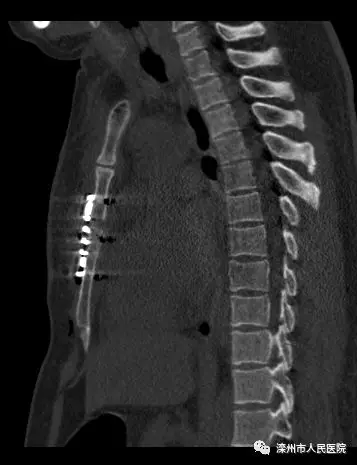

術(shù)后影像

本次手術(shù)改變以往行鋼絲縫合的方法,改用環(huán)抱式胸骨固定器,既減少了組織分離造成的損傷,又避免了胸骨內(nèi)側(cè)穿鋼絲的意外損傷,而且固定效果滿意。